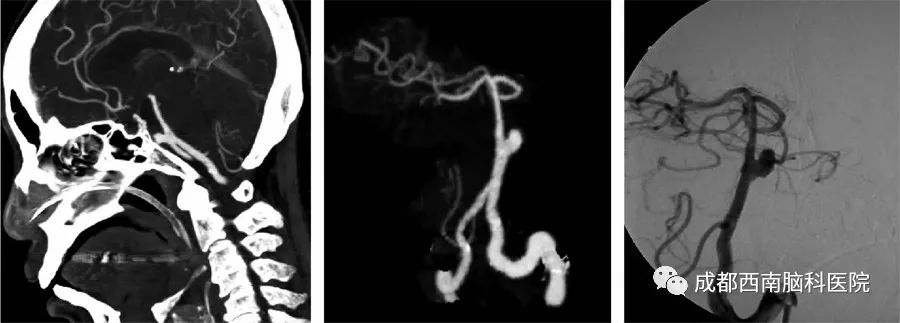

2、颅内动脉瘤的筛查,目前只有头颅CTA和头颅MRA靠谱。如果头颅CTA/MRA有疑问,可以考虑行全脑DSA确定诊断。三维脑血管造影(3D-DSA)是脑血管病精准诊断的金标准,但DSA一般不用于体检,而用于最后的确诊和介入治疗。